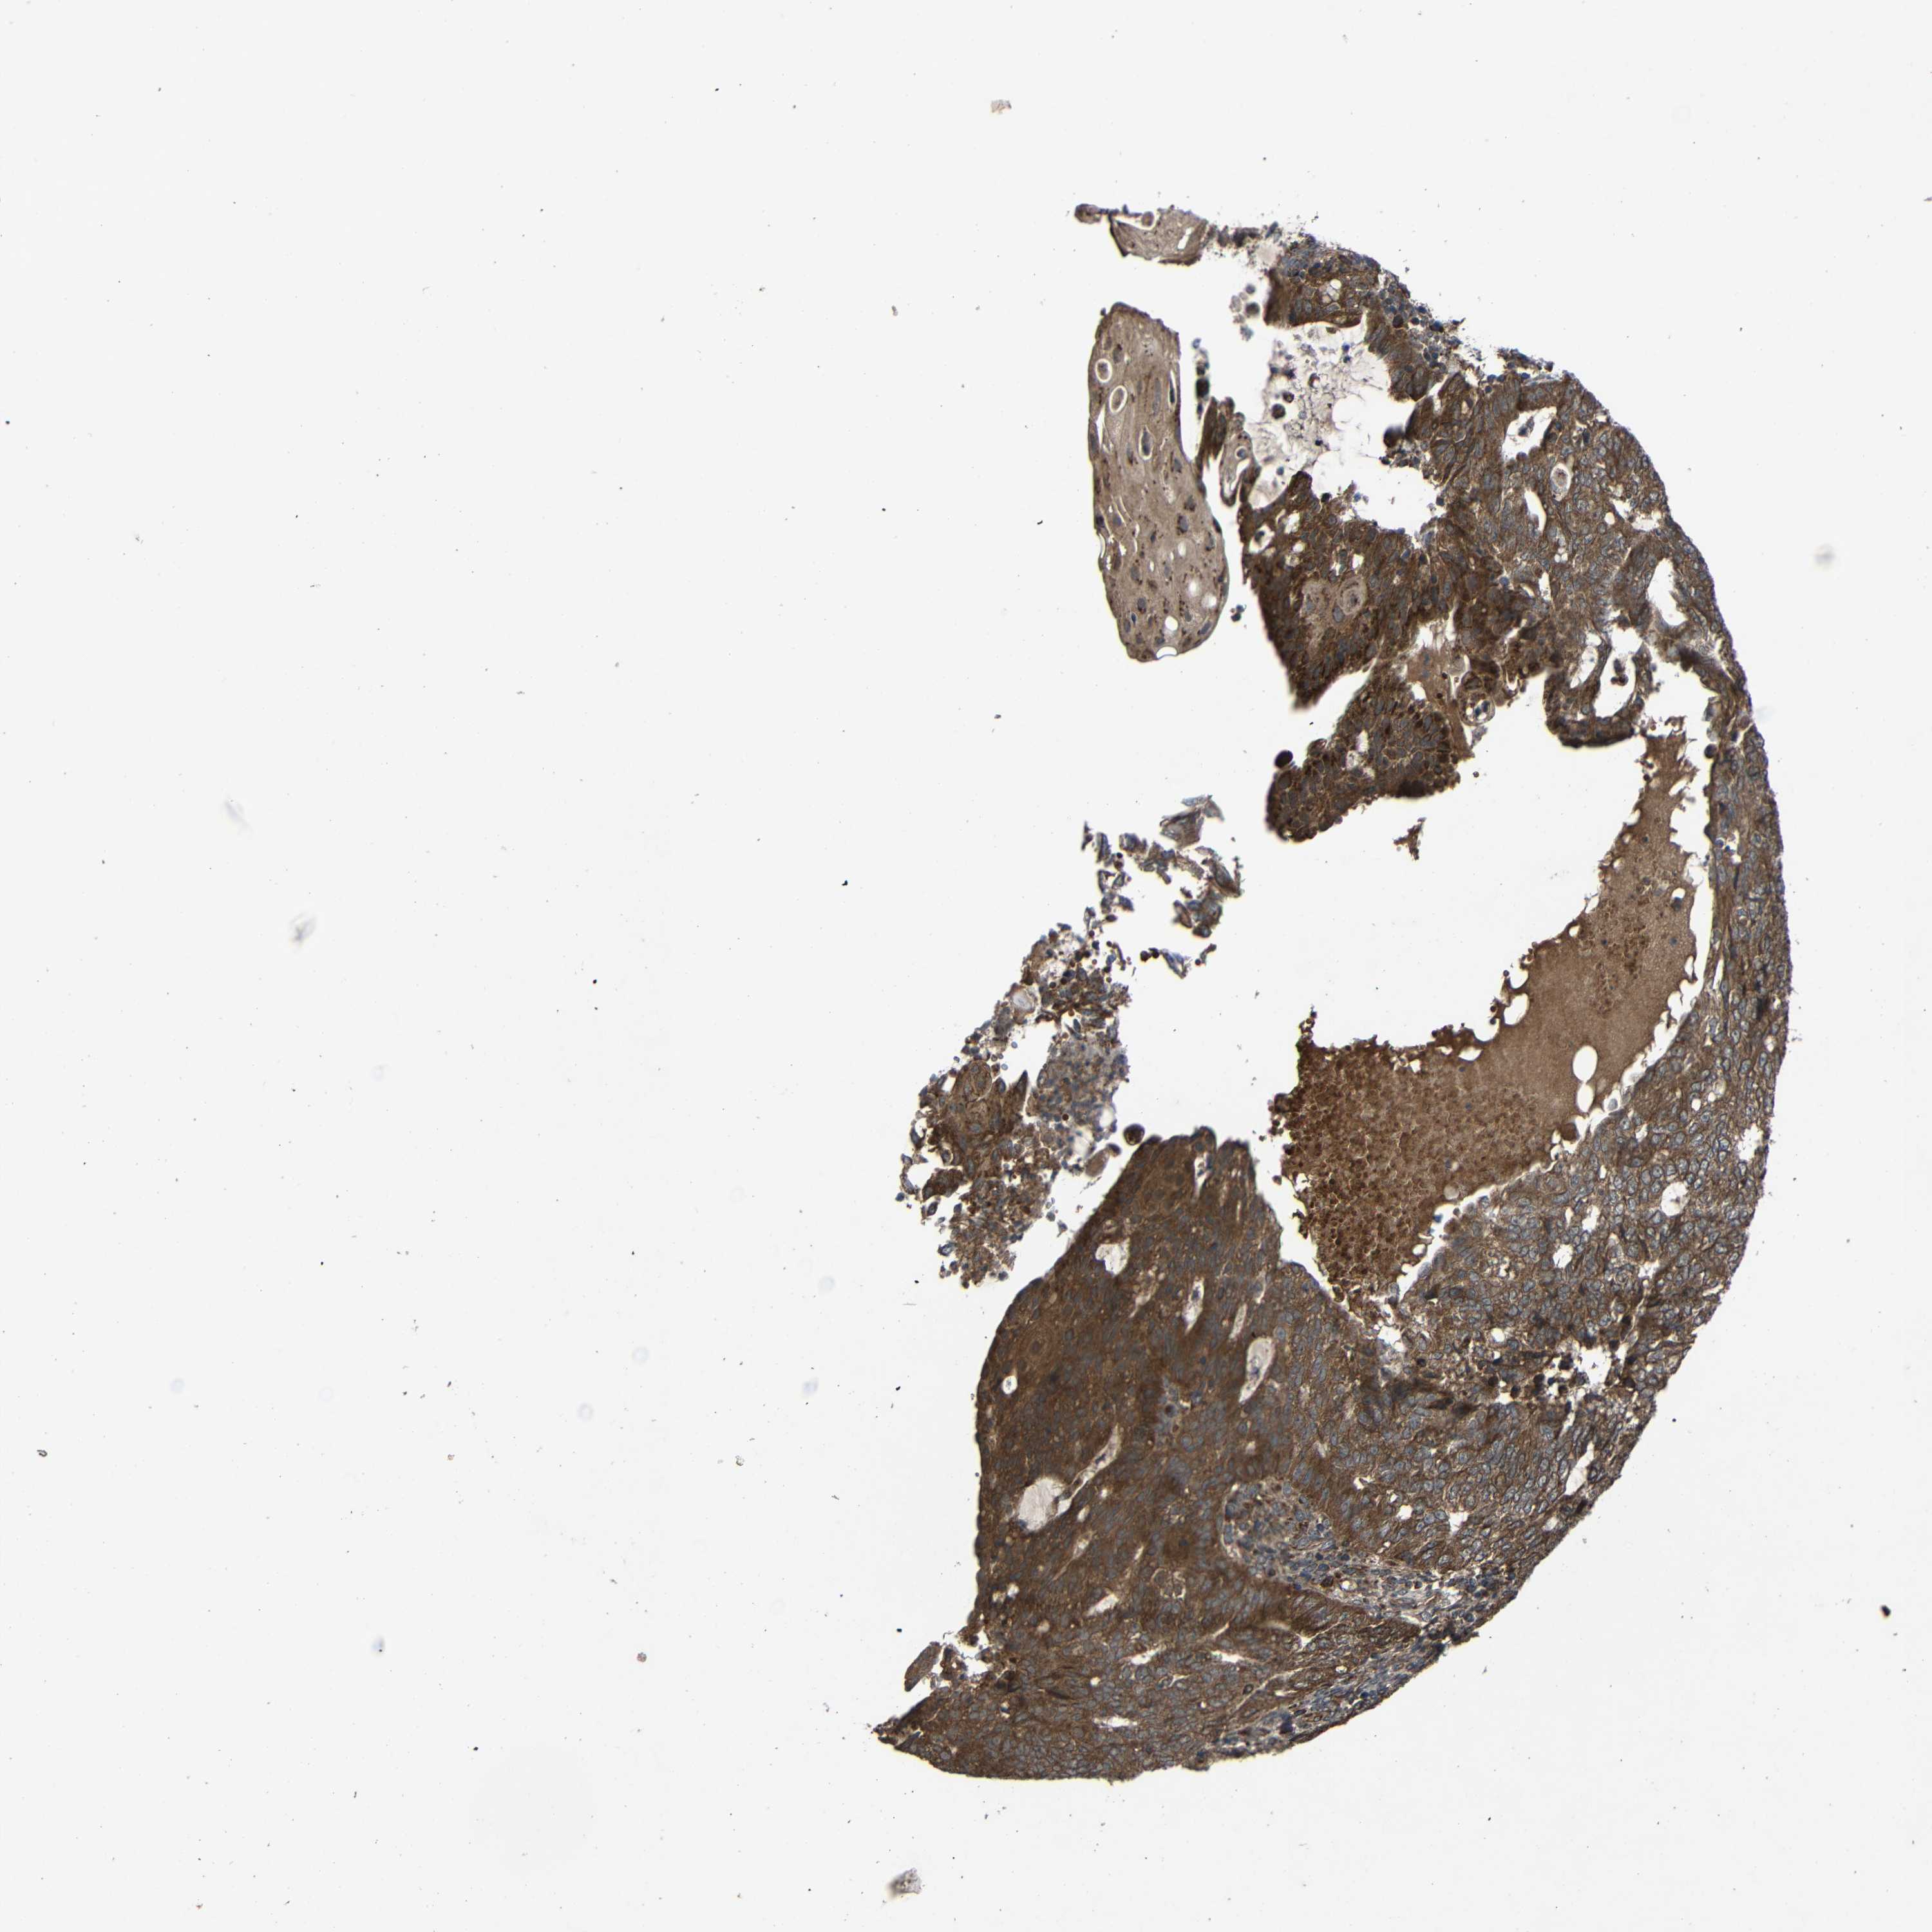

ENDOMETRIAL CANCER - Protein expressioni

A mouse-over function shows sample information and annotation data. Click on an image to view it in a full screen mode. Samples can be filtered based on level of antibody staining by selecting one or several of the following categories: high, medium, low and not detected. The assay and annotation is described here.

Note that samples used for immunohistochemistry by the Human Protein Atlas do not correspond to samples in the TCGA dataset.

Antibody stainingi

Antibody staining in the annotated cell types in the current human tissue is reported as not detected, low, medium, or high, based on conventional immunohistochemistry profiling in selected tissues. This score is based on the combination of the staining intensity and fraction of stained cells.

Each image is clickable and will lead to virtual microscopy that enables deeper exploration of all samples and also displays staining intensity scores, fraction scores and subcellular localization as well as patient and tissue information for each sample.

Antibody HPA011294

Antibody HPA012819

Staining

High

Medium

Low

Not detected

Intensity

Strong

Moderate

Weak

Negative

Quantity

>75%

75%-25%

<25%

None

Location

Nuclear

Cytoplasmic/membranous

Cytoplasmic/membranous,nuclear

Adenocarcinoma, NOS